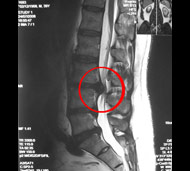

Чтобы определить, есть ли у вас межпозвонковая грыжа, врач соберет анамнез и проведет неврологическое обследование. В частности, он проверит симптомы, указывающие на сдавление нервных структур, а при их наличии исследует, насколько эти структуры потеряли свою функцию. Однако решающими в диагностике заболеваний позвоночника являются такие методы обследования, как:

- Магнитно-резонансная томография (МРТ). Для создания изображений вашего тела используется магнитное поле. Это исследование применяется для подтверждения локализации грыжи межпозвоночного диска и определения пораженных нервов. МРТ является золотым стандартом диагностики грыж межпозвонковых дисков.

![]()  |